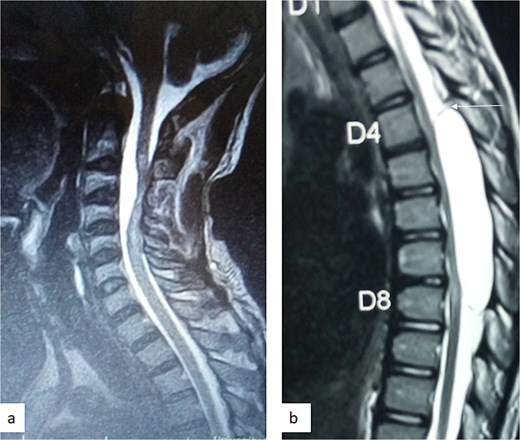

A 12-year-old girl presented to us with progressive weakness of the lower limbs of 11 months duration. There was associated paraesthesia and spasms but no sphincteric dysfunction. Clinical examination revealed an otherwise healthy young girl with normal mental status. She had spastic paraparesis (power Grades 3 to 4) and exaggerated muscle stretch reflexes in the lower limbs. The sensory level was T4. There was no gibbus or spinal tenderness. Other systemic examination findings were normal. A clinical diagnosis of T4 non-traumatic myelopathy, Frankel D was made. Thoracic spine MRI showed an extradural lesion with similar intensities to CSF on all sequences posterior to the spinal cord at T4–T8 as well as significant cord compression at the same levels (Fig. 3) [12]. A diagnosis of thoracic spine EAC was made. We approached the lesion through T4–T8 laminectomies. Intra-operative finding was that of a large extradural cyst which communicated with the subarachnoid space through a dorsolaterally located pedicle near the nerve sleeve at T7. The cyst was excised completely and the dura defect closed without duroplasty (Fig. 4) [12]. The post-operative course was uneventful and she was discharged on the 24th post-operative day. She was last seen 48 months post-surgery. At the time, she was ambulating without support with power of Grade 5 in the lower limbs.

![Sagittal T1-weighted (a) and T2-weighted (b) thoracic spine MRI showing an extradural cyst at T4–T8 compressing the cord anteriorly [12].](https://oupdevcdn.silverchair-staging.com/oup/backfile/Content_public/Journal/jscr/2025/5/10.1093_jscr_rjaf331/1/m_rjaf331f3.jpeg?Expires=1775813958&Signature=Iw-LBqf5WmYRnV3WrYh2T9vqw3hXcashWao2jpou1bclcoxgkvCymBlx06JDIuzVoO9iKmc1lYcyxH0Ib2AT29-s5bhyqwm7W4TElsFo6S-EIEyBs1KAKcn7mOE-zb22PEvpgx2nIG3F60rDFxjzPhLsEWBaeOdNiU4ps5IN5toOnX7S1c7wTj65YvOcL3Q83Na1Du9jN2nYN37Oy22wJTR9mpjT~RP8xEcvJkix80pt2AhMBudcPyU1aBqnnC0ctAgHxyYDC3Iz0dC0E1fw8PjC0hiAryB1Zn30l0MtPh9Gb2eizBBfCIlXJfrdvNTgPjok8R9KahZ68bVLrzHLWw__&Key-Pair-Id=APKAIYYTVHKX7JZB5EAA)

Sagittal T1-weighted (a) and T2-weighted (b) thoracic spine MRI showing an extradural cyst at T4–T8 compressing the cord anteriorly [12].

MRI is the imaging modality of choice for the diagnosis and follow-up of SACs [4]. It does not require intrathecal injection of contrast and demonstrates the location, size, extent, and nature of the cysts as well as neural elements compression and intrinsic cord changes among other features [7, 16–18]. On MRI SACs have similar signal intensities to those of CSF, hypointense on T1-weighted, and hyperintense on T2-weighted images [16]. Extradural cysts may show absent posterior epidural fat, epidural fat capping, and T2-hypointense cyst wall [16, 19, 20] (Figs 3 and 6b). Intradural cysts are characterized by widening of the subarachnoid space, displacement of the cord/cord compression and an undistinguishable cyst wall [2, 21] (Fig. 1). The site of communication between the cysts and subarachnoid may not be demonstrable on MRI [16]. Computed tomography myelograghy has been the imaging of choice in demonstrating the communicating site between the cyst and the subarachnoid cyst [16]. Newer MRI flow studies using cinematic MRI has proven to also be able to demonstrate the communication site [22].

(a) Sagittal T2-weighted cervical spine MRI image showing expanded subarachnoid space anterior to the spinal cord at C2–C4, posterior displacement and compression of the cord and cord signal change at C2–C5. The wall of the cyst is indistinguishable suggestive of intradural spinal arachnoid cyst. (b) Sagittal T2-weighted thoracic MRI image showing compression of the spinal cord anteriorly. There is visible hypointense cyst wall (arrow) suggestive of extradural cyst.